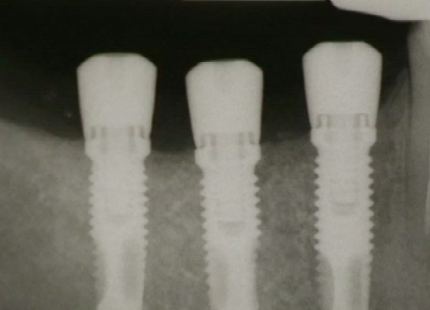

CLINICAL VIDEO Vertical Augmentation, membrane removal and implant placement

Vertical Augmentation, membrane removal and implant placement

Simultaneous Vertical Hard and Soft Tissue Augmentation